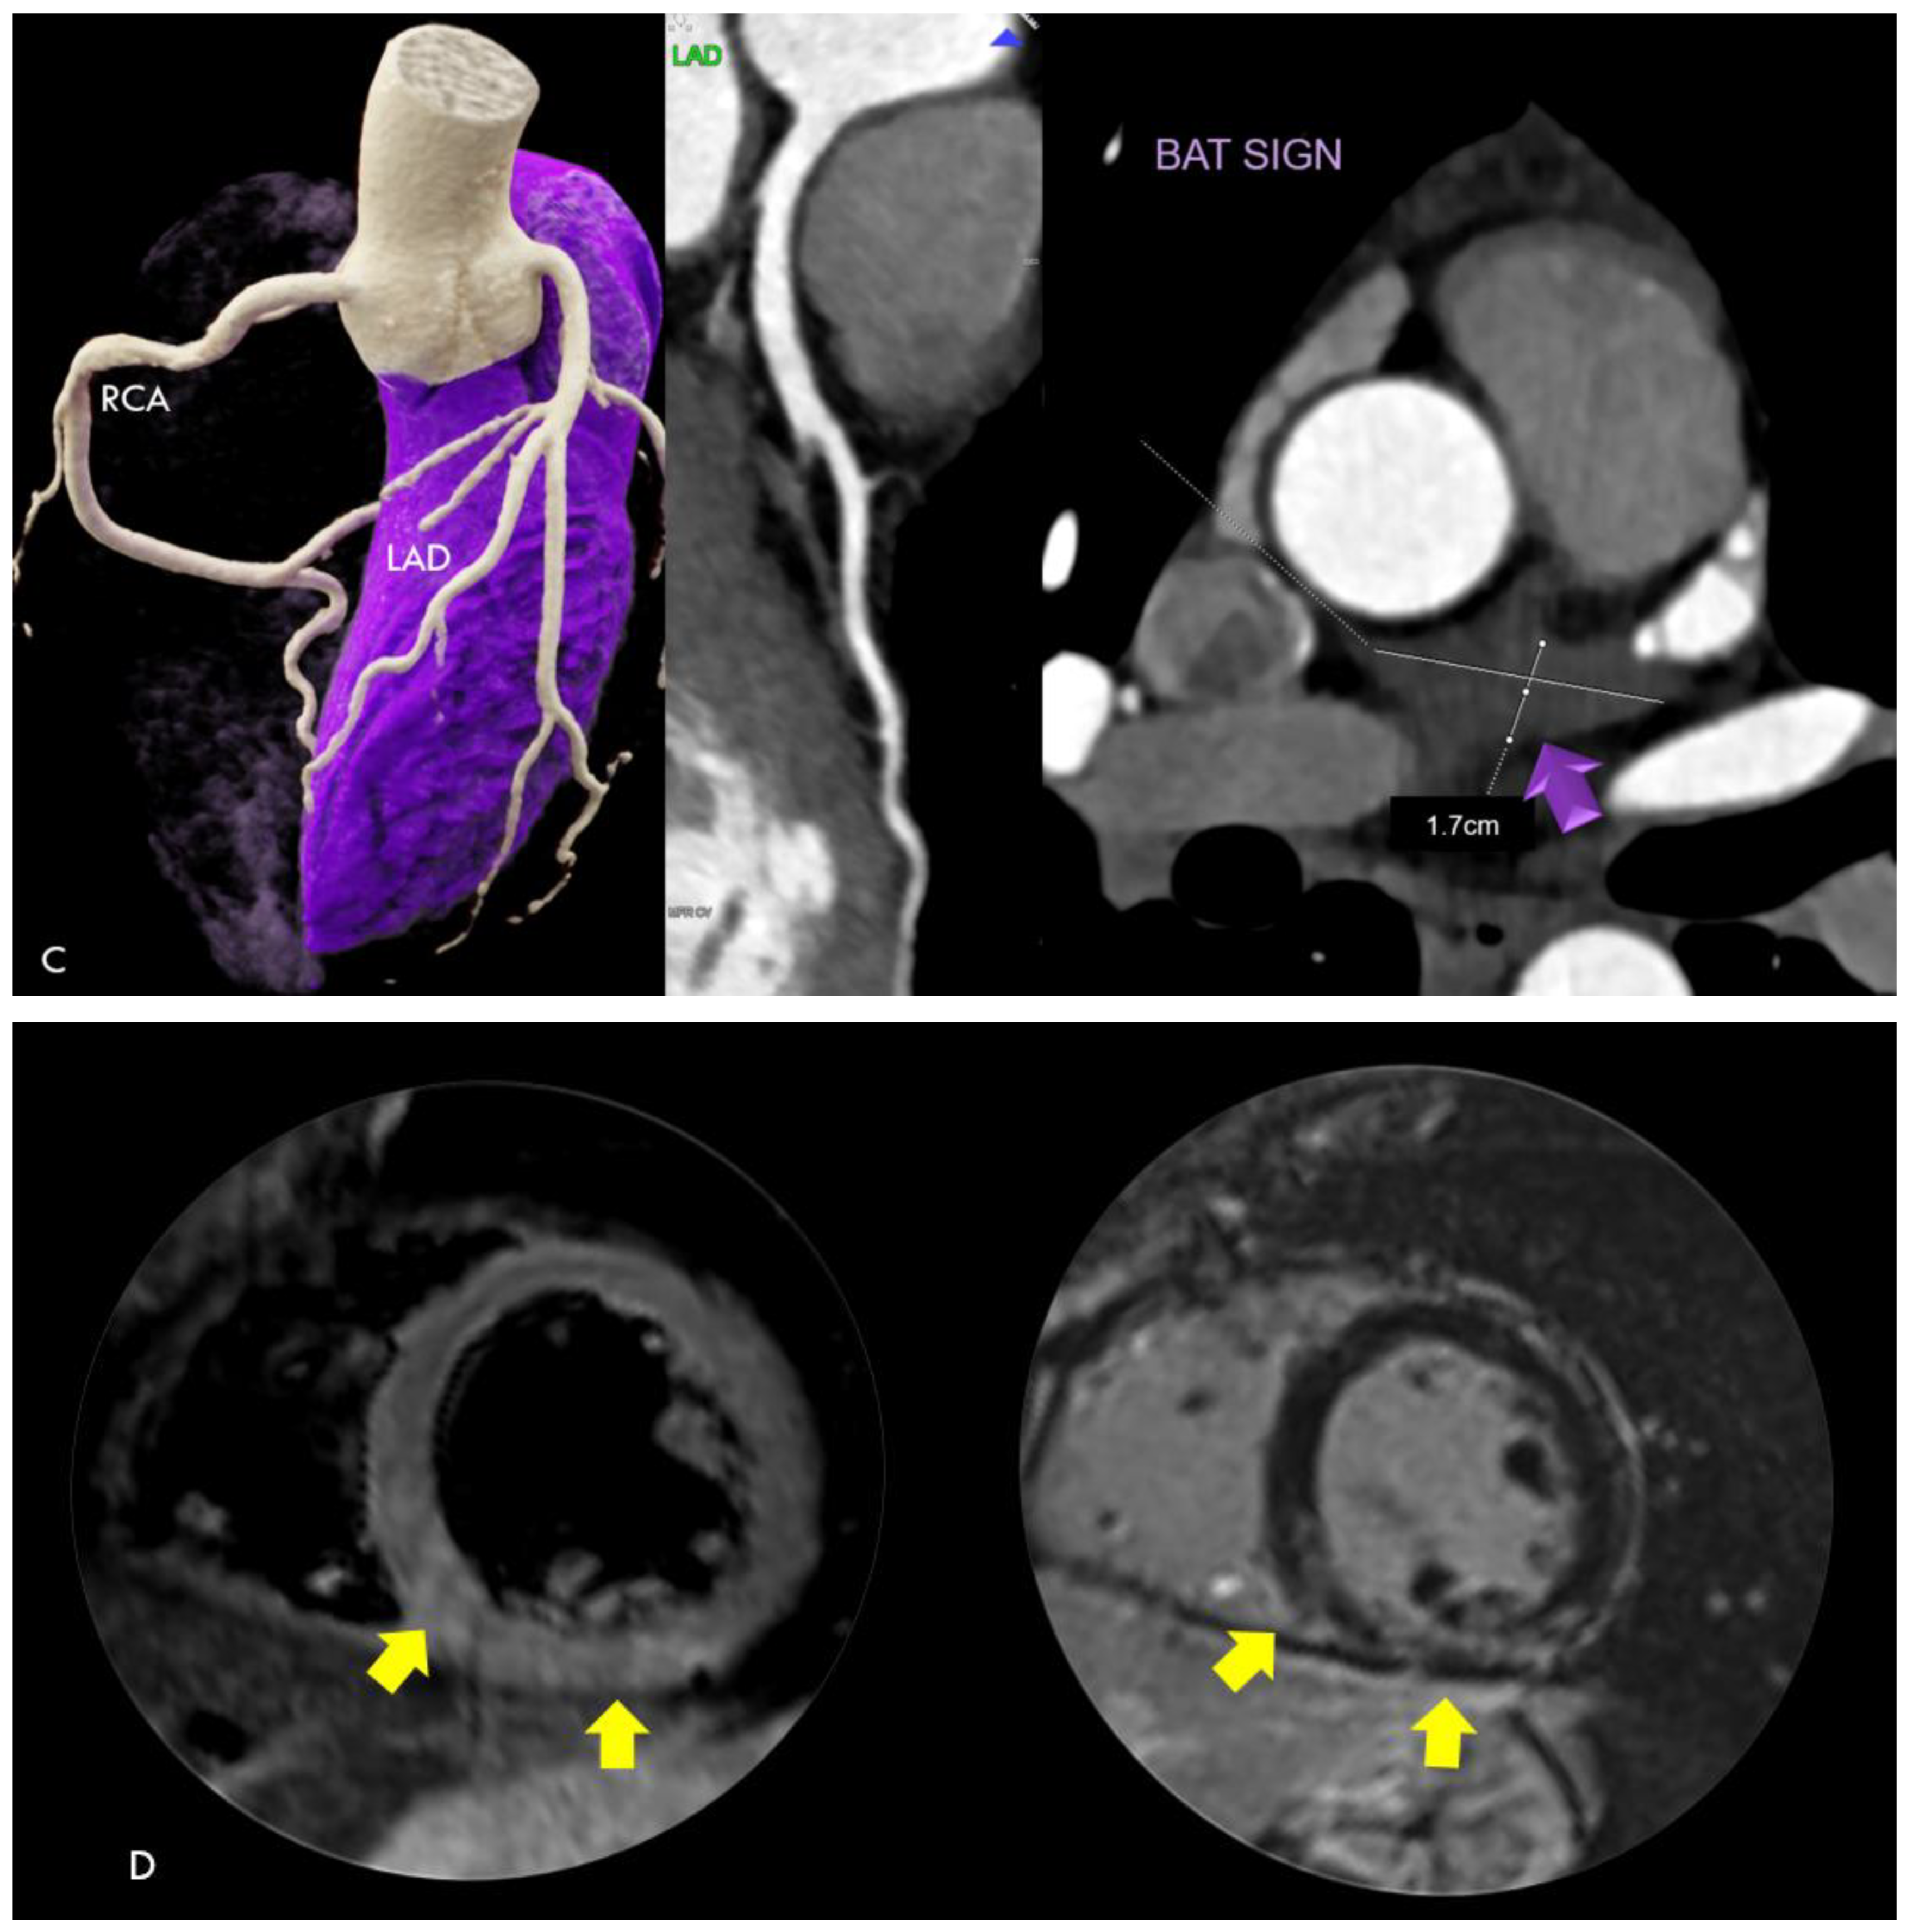

| CTA findings | ||

| Acute, unstable N = 4 | Stable N = 8 | |

| Pericardial effusion | 4 (100%) | 2 (25%) |

| Plaque rupture/ACS | 1 (25%) | 0 (0%) |

| MINOCA | 2 (50%) | 0 (0%) |

| Hyperenhancing myocardium | 1 (25%) | 0 (0%) |

| Perivascular inflammation (PCAT+) | 4 (100%) | 2 (25%) |

| Coronary artery disease by CTA | 1 (25%) | 4 (50%) |

| Nonobstructive (<50% stenosis) | 0 (0%) | 2 (25%) |

| Obstructive (>50% stenosis) | 1 (25%) | 2 (25%) |

| Diffuse vessel wall irregularities | 2 (50%) | 3 (37.5%) |

| Focal ectasia | 0 (0%) | (12.5%) |